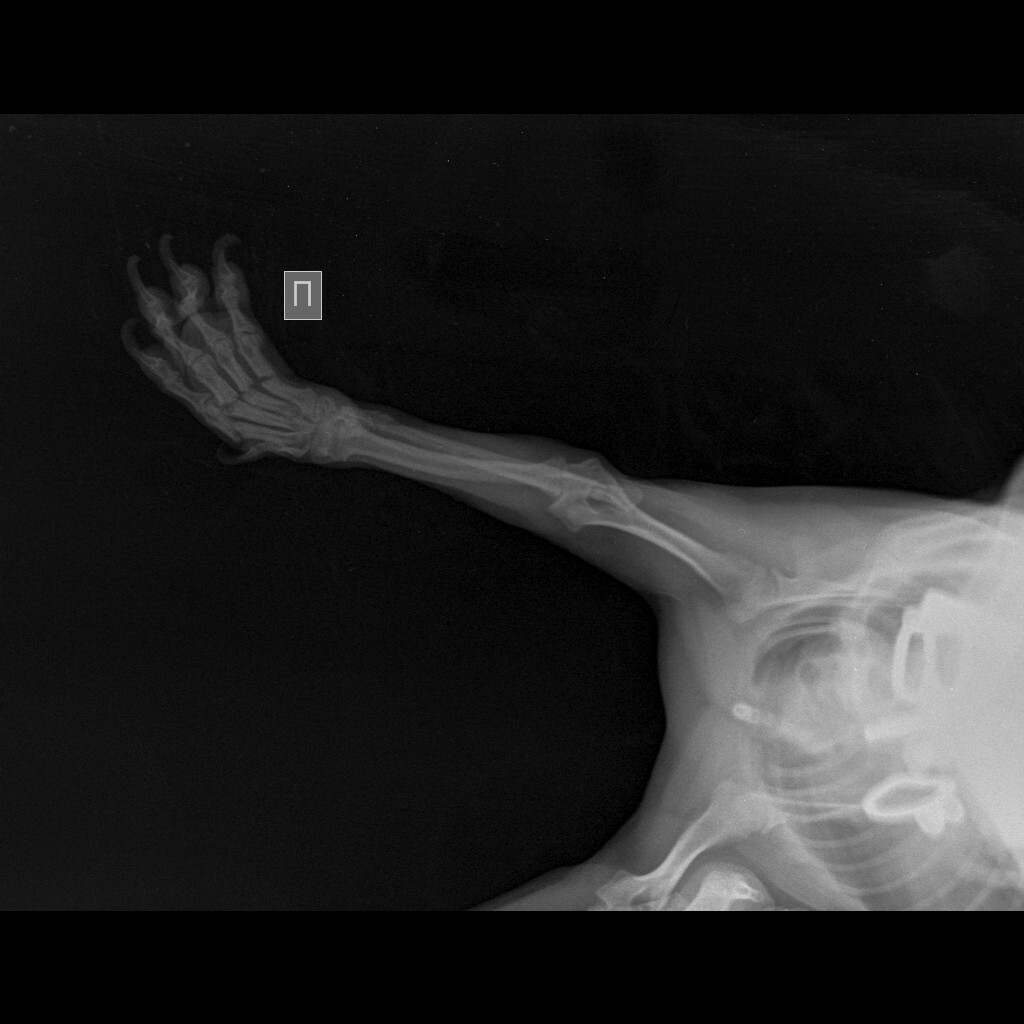

Вопрос вот в чем, щенок йоркширского терьера сломал 4 пальца на лапке. Ветеринарная клиника нашего небольшого города рекомендует делать операцию. Другой врач, в клинике побольше советует ничего не делать. Кому верить?

Вот на этом снимке хорошо виден перелом